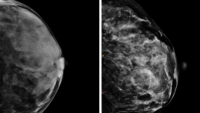

CIMBID is a multidisciplinary center based in the Department of Radiology of the Vagelos College of Physicians and Surgeons (VP&S). This vibrant scientific ecosystem brings together a broad range of expertise with a breadth of cross-campus initiatives and collaborations.